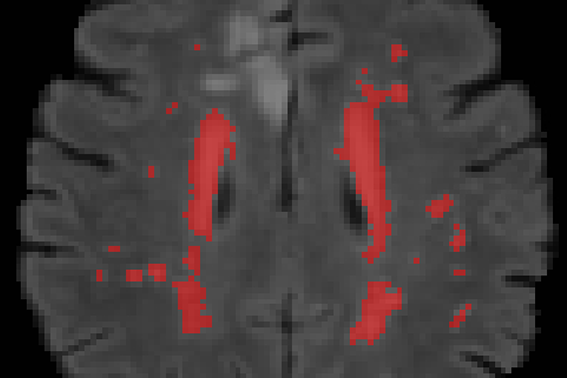

Mona K. Beyer – overlege ved Avdeling for radiologi og nukleærmedisin, Oslo universitetssykehus og professor ved Institutt for klinisk medisin, Universitetet i Oslo – mener det er viktig å ta gode CT- og MR-bilder av hjernen når folk får hjerneslag.

Beyer er spesielt opptatt av årsakssammenhenger og har sett spesielt på hva som karakteriserer hjernen til de pasientene som får problemer etter hjerneslag.

- Vi kan se etter symptomer og forandringer, både over kort og lang tid, og se det i sammenheng med de andre undersøkelsene av hjernen. Vi ser at mange av dem som er med i studien har forandringer i hjernen allerede før de kommer inn. Hva betyr det, og hva har det å si for hvordan det går med pasienten videre? Her har vi mer arbeid å gjøre, sier Beyer.

Slik så et av fotoene av hjernen ut